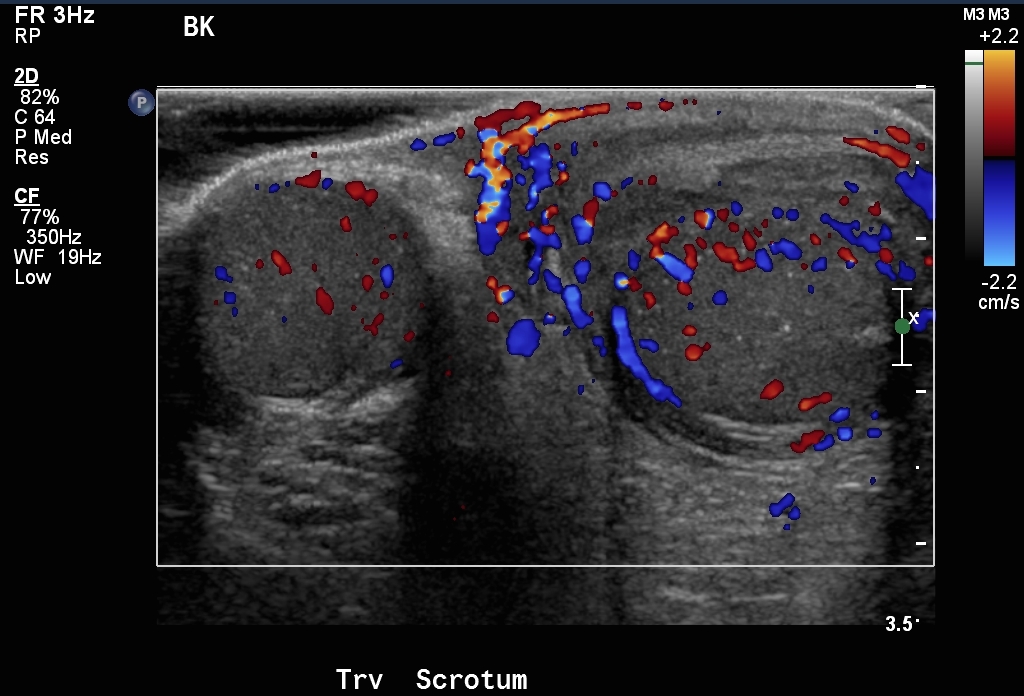

Στις περισσότερες περιπτώσεις ό Υπερηχογραφικός έλεγχος , θα δώσει πολύ μεγάλη βοήθεια στην διάγνωση της ασθένειας με στόχο την άμεση αντιμετώπιση. Αυτά πού μπορούμε να αξιολογήσουμε με το Υπερηχογράφημα και το έγχρωμο Doppler όρχεως , είναι ή ύπαρξη ή όχι αιματικής ροής στον όρχι για διάγνωση της συστροφής ή της φλεγμονής και βέβαια και σαφείς εικόνες ρήξης ορχικού παρεγχύματος , πιθανής συλλογής πύου ή και αίματος στο όσχεο , όγκους όρχεων ή και πιθανές κήλες. Η αντιμετώπιση της κατάστασης εξαρτάται από την αιτία, με την συστροφή όρχεως να απαιτεί την άμεση χειρουργική αποκατάσταση στην περίπτωση αποτυχίας των συντηρητικών χειρισμών.